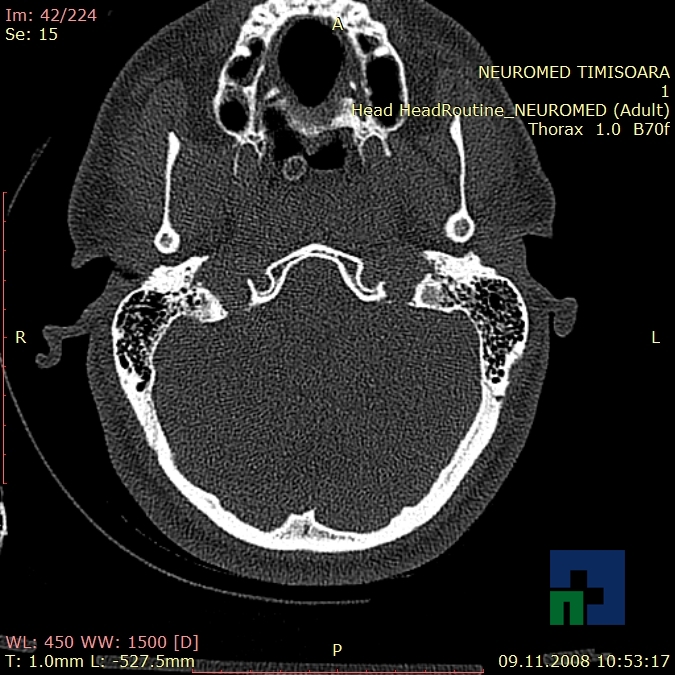

În cazul traumatismelor cranio-cerebrale:

- Diagnosticul edemului cerebral, a contuziei cerebrale, a leziunilor axonale difuze edematoase/hemoragice, a dilacerării cerebrale, a hematomului intraparenchimatos posttraumatic, a hematoamelor subdurale/extradurale (acute, subacute, cronice), a hemoragiei intraventriculare, a hemoragiei subarahnoidiene

- Diagnosticul traumatismelor de bază de craniu

- Diagnosticul fracturilor:

-

- Unice

- Multiple

- Cu înfundare

- Complexe cranio-sinusale

- Complexe cranio-etmoidale

- Complexe cranio-orbitare

- Complexe cranio-faciale